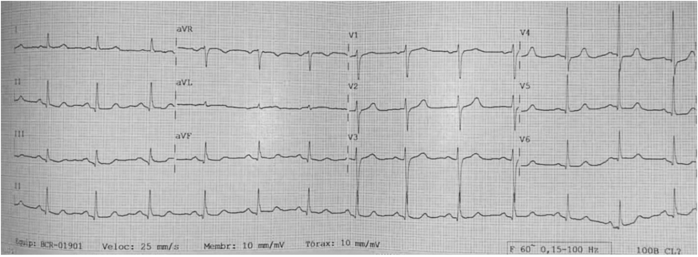

Analise o eletrocardiograma a seguir.

Este exame foi apresentado por uma paciente de 72 anos, com quadro de hipotensão postural nos dias quentes.

Qual o diagnóstico eletrocardiográfico?